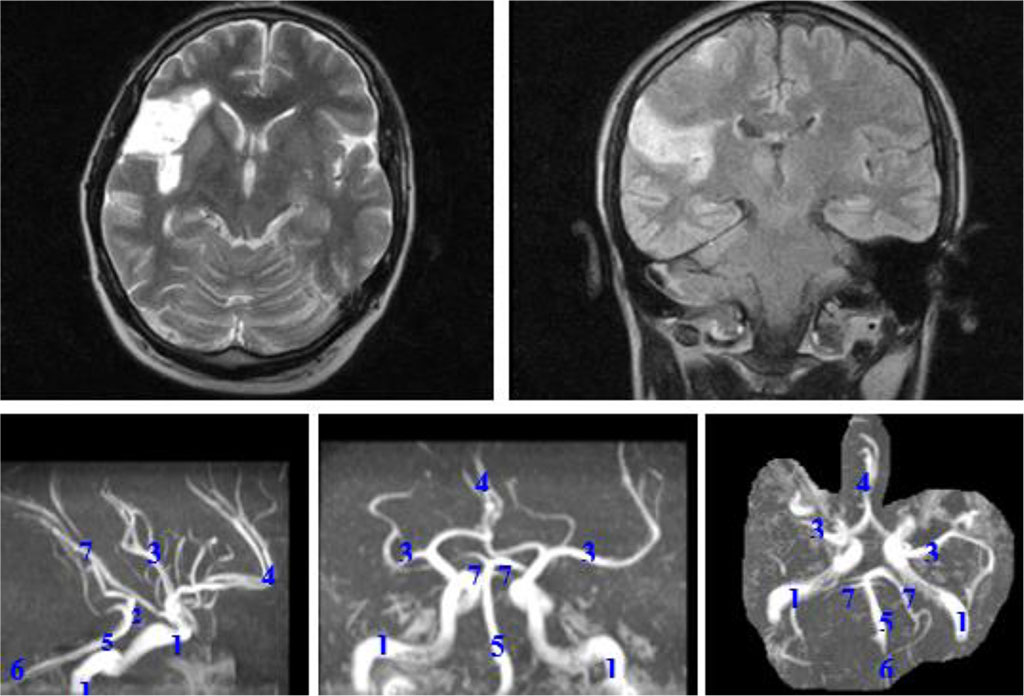

Patient M., 53 years old, unemployed. He underwent examination and treatment in the neurological department of the City Hospital No. 4 in Tambov. He was admitted with complaints of weakness in the left limbs. He had been sick for about 2 months, when gradually began to feel weakness of the left limbs. He went to seek medical help, "because the arm and leg grew completely numb". He was treated in the neurological department of the district hospital at the place of residence with a diagnosis of "Ischemic stroke in the system of the right middle cerebral artery in presence of chronic alcohol intoxication" without a clear effect. Anamnesis: infrequent colds, long-term abuse of alcohol and its surrogates, as well as smoking. He categorically denied any other diseases. MRI of the brain: In the right hemisphere of the brain: massive cerebrovascular disorders associated with dyscirculation. Median structures were not displaced. The ventricles were dilated to 1-2 degree. 4th ventricle was in the midline. The pituitary gland was not enlarged. MRA: Posterior trifurcation of the right internal carotid artery, hypoplasia of both posterior communicating arteries. See the Figure 1.

Figure 1. MRI: postischemic changes in the right hemisphere. Magnetic resonance angiography: posterior trifurcation of the right internal carotid artery, hypoplasia of both posterior communicating arteries. 1 - internal carotid arteries; 2 - posterior communicating arteries; 3 - middle cerebral arteries; 4 - anterior cerebral artery; 5 - basilar artery; 6 - vertebral arteries; 7 - posterior cerebral arteries.